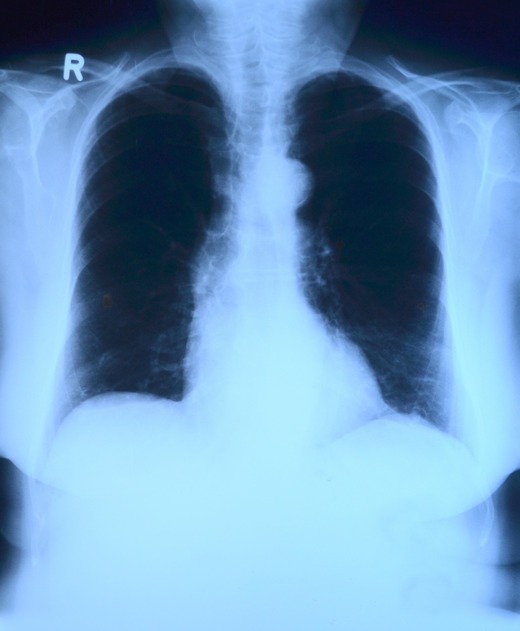

Potrivit statisticilor, în fiecare an, în România sunt diagnosticate peste 11.000 de cazuri noi de cancer pulmonar diagnosticate, 75% dintre acestea în stadii avansate, când opțiunile terapeutice sunt limitate. Peste 10.000 de persoane și-au pierdut viața în 2018 din cauza acestei afecțiuni.

"Rolul medicului de familie este extrem de important, fiind primul punct de contact al pacientului cu sistemul de sănătate și cel care poate interpreta simptomele și evalua riscul de cancer pulmonar, în funcție de care poate trimite pacientul către un medic pneumolog pentru un diagnostic de precizie. Recomand persoanelor ce manifestă o tuse persistentă, respirație îngreunată, scădere în greutate, să meargă la medicul de familie pentru un consult amănunțit. Din perspectiva politicilor de sănătate, se impune implementarea unei proceduri accelerate de diagnostic, pentru a elimina timpii ce se pierd de la identificarea simptomelor specifice la diagnosticare și mai apoi tratament", a declarat dr. Dina Mergeani, președinte al Societății Naționale de Medicina Familiei (SNMF), potrivit sursei citate.